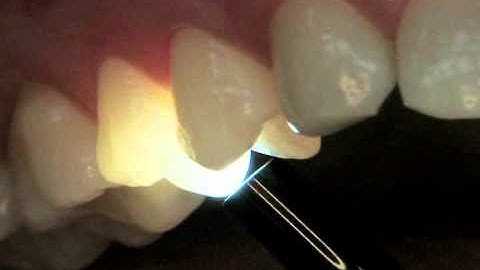

Why Pediatric Dentists Should be Using Transillumination for Caries Detection